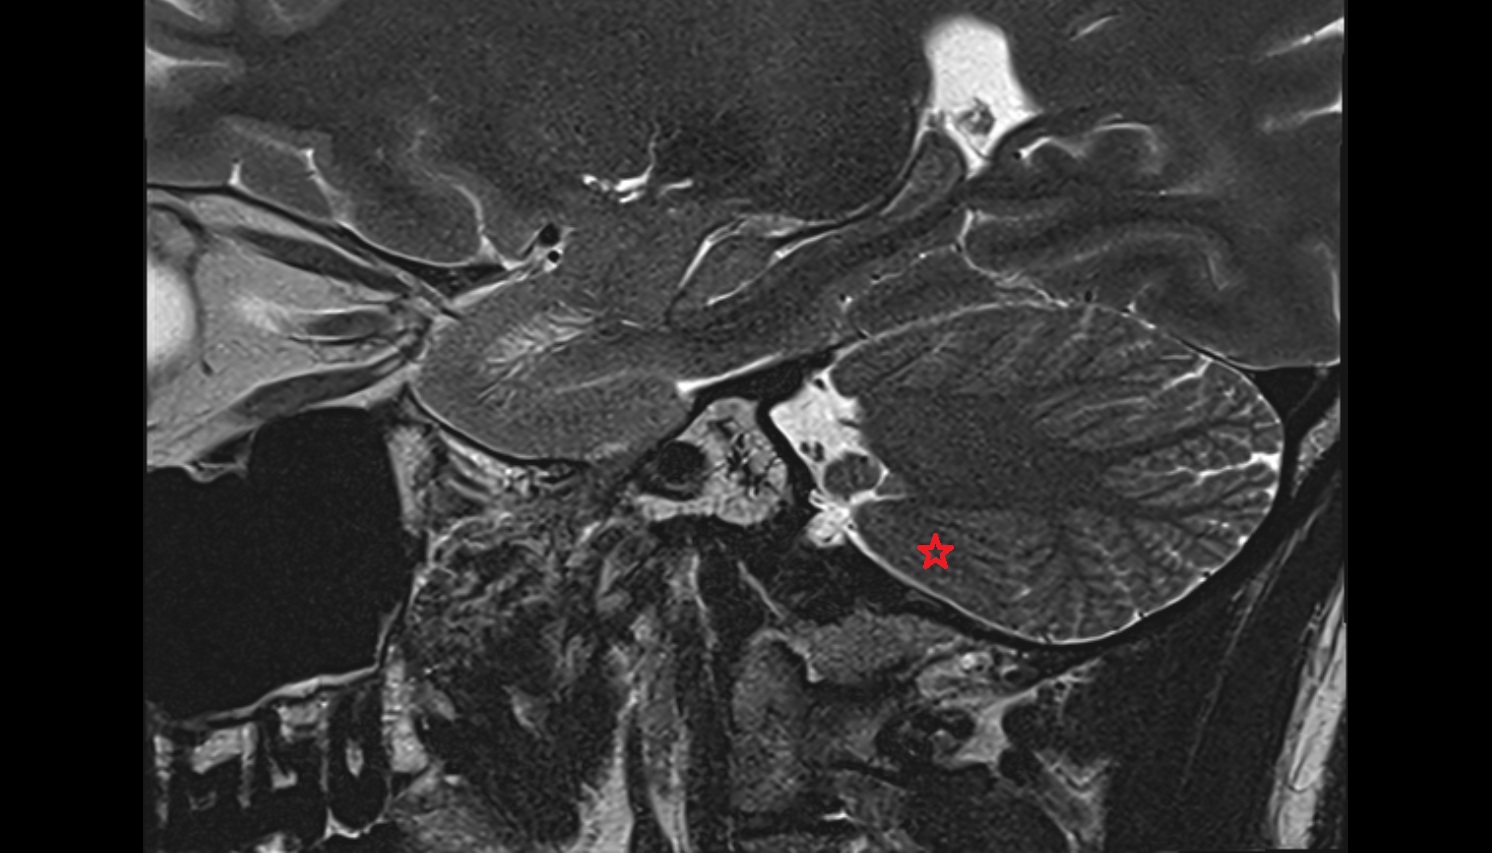

- Temporomandibular joint

- Mandibular condyle

- Mandibular fossa

- Articular disc of temporomandibular joint

- Articular eminence